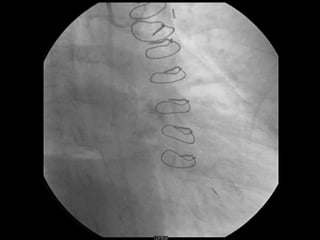

POSICIONAMENTO FILTRO DE PROTEÇÃO DISTAL

POSICIONAMENTO FILTRO DEPROTEÇÃO DISTAL